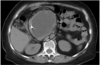

Pancreatic pseudocyst

40

Necrotizing pancretitis